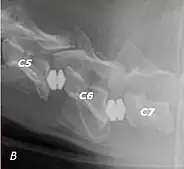

The disease tends to be gradually progressive. Symptoms such as weakness, ataxia, and dragging of the toes start in the rear legs. Dogs often have a crouching stance with a downward flexed neck. The disease progresses to the front legs, but the symptoms are less severe. Neck pain is sometimes seen. Symptoms are usually gradual in onset, but may progress rapidly following trauma.[6] X-rays may show misaligned vertebrae and narrow disk spaces, but it is not as effective as a myelogram, which reveals stenosis of the vertebral canal. Magnetic resonance imaging has been shown to be more effective at showing the location, nature, and severity of spinal cord compression than a myelogram.[7] Treatment is either medical to control the symptoms, usually with corticosteroids and cage rest, or surgical to correct the spinal cord compression. The prognosis is guarded in either case. Surgery may fully correct the problem, but it is technically difficult and relapses may occur. Types of surgery include ventral decompression of the spinal cord (ventral slot technique), dorsal decompression, and vertebral stabilization.[8] One study showed no significant advantage to any of the common spinal cord decompression procedures.[9] Another study showed that electroacupuncture may be a successful treatment for Wobbler disease.[10] A new surgical treatment using a proprietary medical device has been developed for dogs with disc-associated wobbler disease. It implants an artificial disc (cervical arthroplasty) in place of the affected disc space.[11]

Wobbler disease is probably inherited in the Borzoi, Great Dane, Doberman, and Basset Hound.[2] Instability of the vertebrae of the neck (usually the caudal neck) causes spinal cord compression. In younger dogs such as Great Danes less than two years of age, wobbler disease is caused by stenosis (narrowing) of the vertebral canal[3] related to degeneration of the dorsal articular facets and subsequent thickening of the associated joint capsules and ligaments.[1] A high-protein diet may contribute to its development.[4] In middle-aged and older dogs such as Dobermans, intervertebral disc disease leads to bulging of the disc or herniation of the disc contents, and the spinal cord is compressed.[3] In Great Danes, the C4 to C6 vertebrae are most commonly affected; in Dobermans, the C5 to C7 vertebrae are affected.[5]

Wobbler disease is definitively diagnosed by x-ray, nuclear scintigraphy or bone scan. X-rays will show channel widening or filling the easiest and are often most cost-effective to horse owners. X-rays will also show any structural anomaly, arthritis, facet remodeling, or bone spurs present. Preliminary diagnosis can be made by ultrasound but x-rays are needed to measure the true depth of facet involvement. For extent of damage to associated structures, veterinarians may opt to have the horse undergo a bone scan or nuclear scintigraphy.